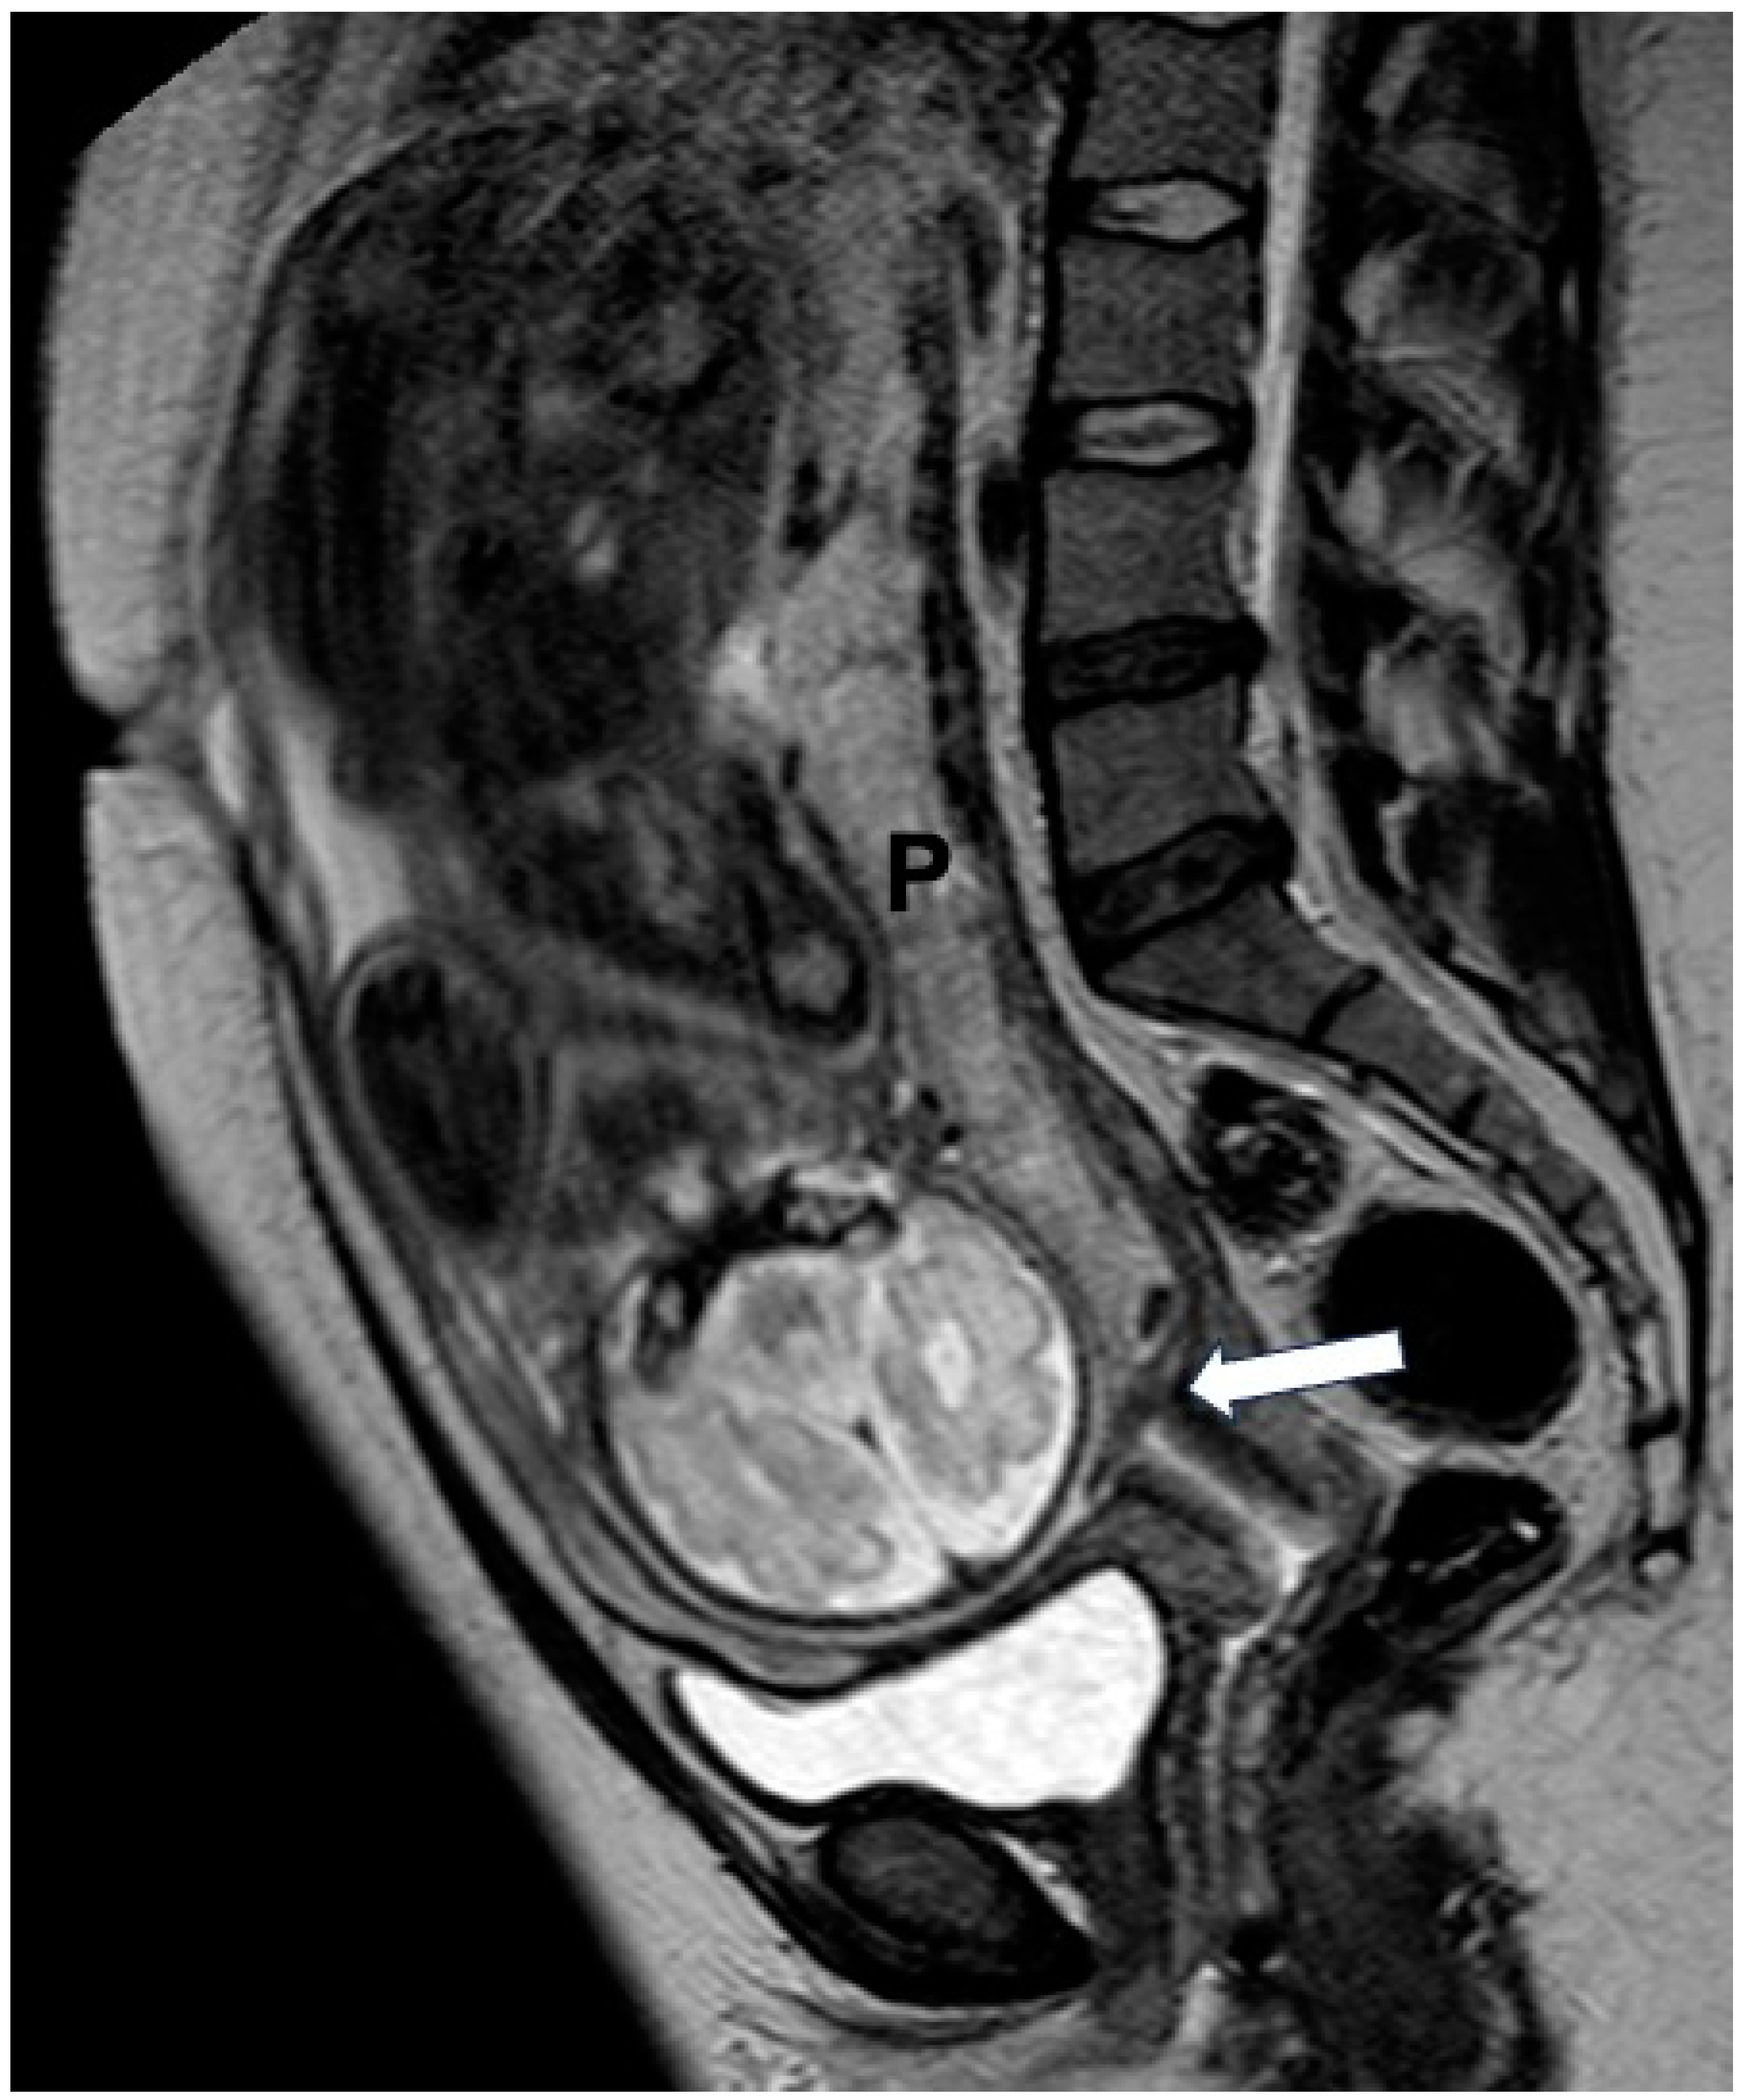

- Bourgioti, C.; Zafeiropoulou, K.; Fotopoulos, S.; Nikolaidou, M.E.; Antoniou, A.; Tzavara, C.; Moulopoulos, L.A. MRI Features Predictive of Invasive Placenta with Extrauterine Spread in High-Risk Gravid Patients: A Prospective Evaluation. Am. J. Roentgenol. 2018, 211, 701–711. [Google Scholar] [CrossRef]

- Bourgioti, C.; Zafeiropoulou, K.; Fotopoulos, S.; Nikolaidou, M.E.; Theodora, M.; Daskalakis, G.; Tzavara, C.; Chatoupis, K.; Panourgias, E.; Antoniou, A.; et al. MRI Prognosticators for Adverse Maternal and Neonatal Clinical Outcome in Patients at High Risk for Placenta Accreta Spectrum (PAS) Disorders. J. Magn. Reson. Imaging 2019, 50, 602–618. [Google Scholar] [CrossRef]

- Bourgioti, C.; Konstantinidou, A.E.; Zafeiropoulou, K.; Antoniou, A.; Fotopoulos, S.; Theodora, M.; Daskalakis, G.; Nikolaidou, M.E.; Tzavara, C.; Letsika, A.; et al. Intraplacental Fetal Vessel Diameter May Help Predict for Placental Invasiveness in Pregnant Women at High Risk for Placenta Accreta Spectrum Disorders. Radiology 2021, 298, 403–412. [Google Scholar] [CrossRef]